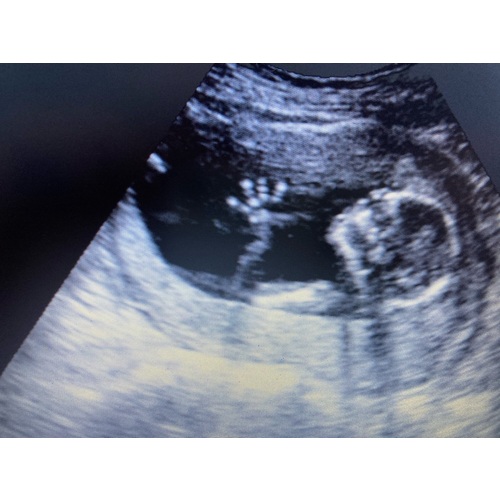

Hi ik heb de baby watcher 3 dagen gehad. Je moet niet het beste kwaliteit verwachten. Je kan niet alles duidelijk er mee zien je kan zien dat je kleine lekker beweegt en met geluk kan je het hartje zien. Bij mij was er gedoe bij het leveren op de dag zelf kregen we te horen dat die niet kwam en toen ik hem wou annuleren kon de baby watcher ineens op de post.

Mijn ervaring is als je zelf een goeie laptop hebt neem daar het pakket op zodat wellicht je beeld veel beter is je krijg hier best oudere laptops bij en de beeld kwaliteit is gewoon niet het beste. Als ik het had geweten had ik me eigen laptop genomen